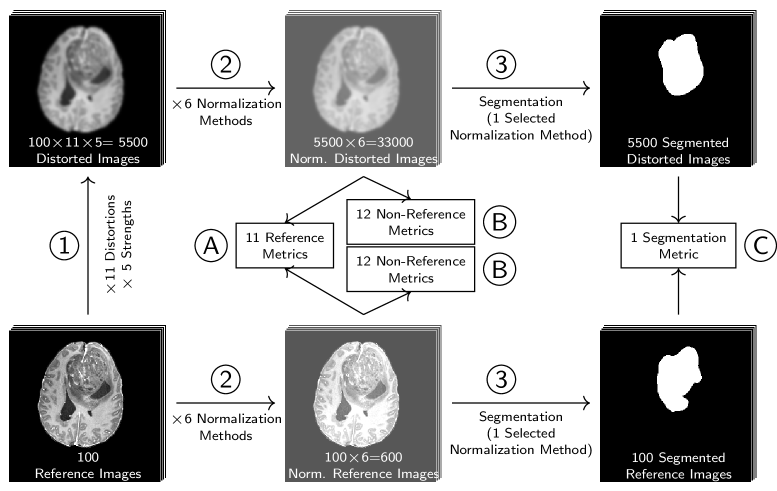

However, validation of these approaches is not straightforward. If a reference image, representing the desired synthesis result, is available for each generated image, a group of metrics called reference metrics can assess the similarity between predicted and reference images (see Fig. 1 (A)). These reference images are often already leveraged for training synthesis models in a paired or supervised manner. Reference metrics are sometimes called full-reference metric to distinguish from weak-reference metrics, that only use partial information or features of the reference image. The term similarity metric is also synonymously used for reference metric.

However, not always paired reference images are available. In this case, non-reference metrics, also called quality metrics, can be applied (see Fig. 1 (B)). As quality requirements may vary between tasks and image domains, metrics for different aspects have been developed, e.g. for measuring blurriness [23], contrast [24], noisiness [25] or other features inspired by human perception [26]. Depending on the application of synthesized images, the evaluation of the images in a downstream task is more appropriate, than the evaluation of the images themselves [27]. Downstream task metrics operate on further processed results and not on the predicted or reference image (see Fig. 1 (C)). For GANs, so-called distribution based metrics are very popular [28]. These assess the distributions of extracted image features of a larger set of generated images. For example, the Inception score [29] assesses how distinct and evenly distributed classes are predicted by an Inception architecture based classifier trained on ImageNet (InceptionNet [30]). And the Frêchet Inception Distance[31] assesses how well Gaussian modeled activation layer distributions of the InceptionNet match between generated and reference image sets. As these metrics do not assess single images, these metrics are not in the scope of this study.

In order to systematically investigate reference and non-reference metrics, we distorted 100 T1-weighted contrast enhanced MR images with 11 different types of distortions in five strengths. For the reference metrics (see Sec. 2.3), the similarity between each distorted image and its undistorted reference was calculated. For the non-reference metrics (see Sec. 2.5), the metric scores for all distorted and undistorted images were assessed. For the segmentation metric (see Sec. 2.4), we trained a model and predicted segmentations for all distorted and undistorted images. The segmentation metric assessed the agreement between segmentations derived from distorted images and segmentations derived from the respective undistorted reference image. In addition, images individually normalized with one of six different normalization methods, including no normalization, leaving the images with raw intensity values. The workflow of the experiments is illustrated in Fig. 2. In image-to-image tasks, MR source or target images are typically normalized for model training and the synthesized images are generated in this normalized space. Validation of synthesized images can either be performed in this normalized space, such that the normalized target image is used as reference and the synthesized image is assumed to already be normalized appropriately. Another possibility is to invert the previously performed normalization method on the synthesized image to the original intensity range. Then the synthesized image can be compared to the target image in the original intensity range. In our experiments, we test the metrics in the original and a normalized intensity range. As some distortions slightly or more drastically extend or reduce the intensity range of the reference image, different normalization methods result in different alignment of histograms of the reference and the distorted images. The LPIPS metric requires an input range of [-1 and 1], therefore we decided to apply Minmax and cMinmax normalization to the required target range of . The DISTS metric requires an input range of .. Even though all normalization methods besides Minmax and cMinmax do not satisfy the required input ranges, we did evaluate the metrics after these normalization methods to investigate deviations to the recommended type of normalization.